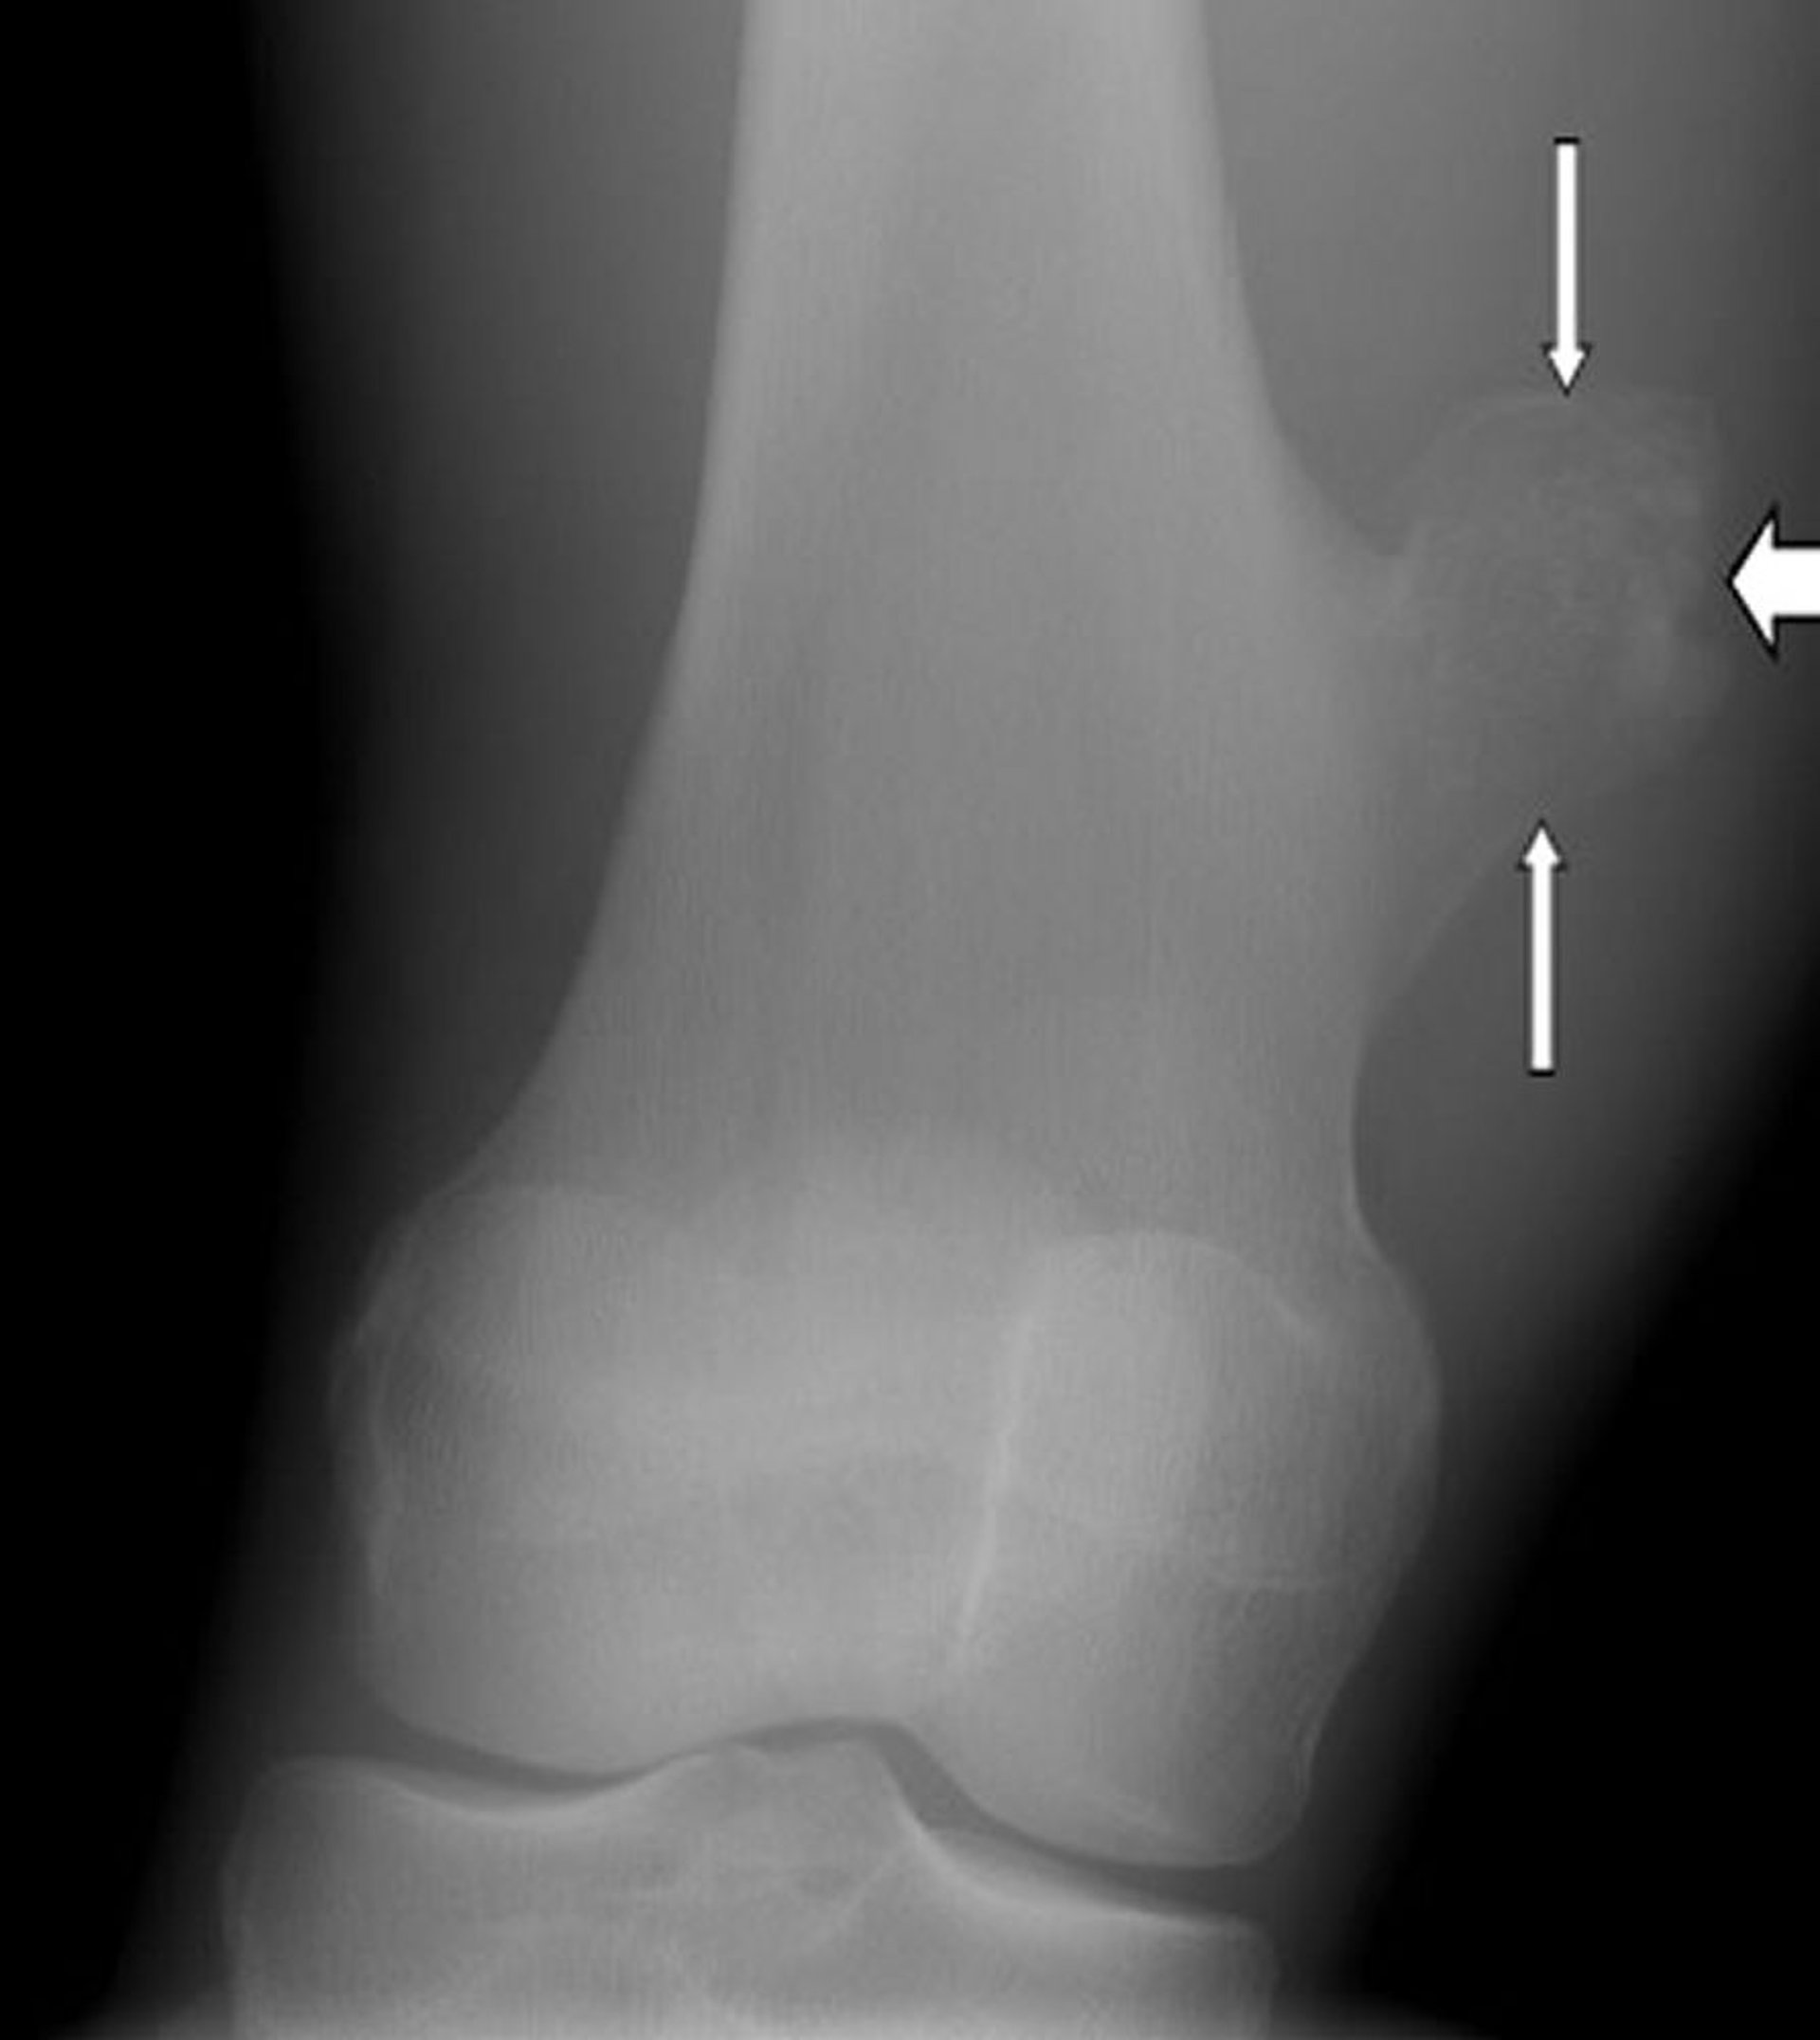

Radiografia che mostra un fibroma non ossificante (frecce) del femore sopra al ginocchio.

Per gentile concessione di Michael J. Joyce, MD e Hakan Ilaslan, MD.

I fibromi non ossificanti piccoli non hanno bisogno di trattamento. Tuttavia, i fibromi che causano dolore o che crescono molto vengono rimossi e nella cavità rimasta viene inserito un innesto osseo.